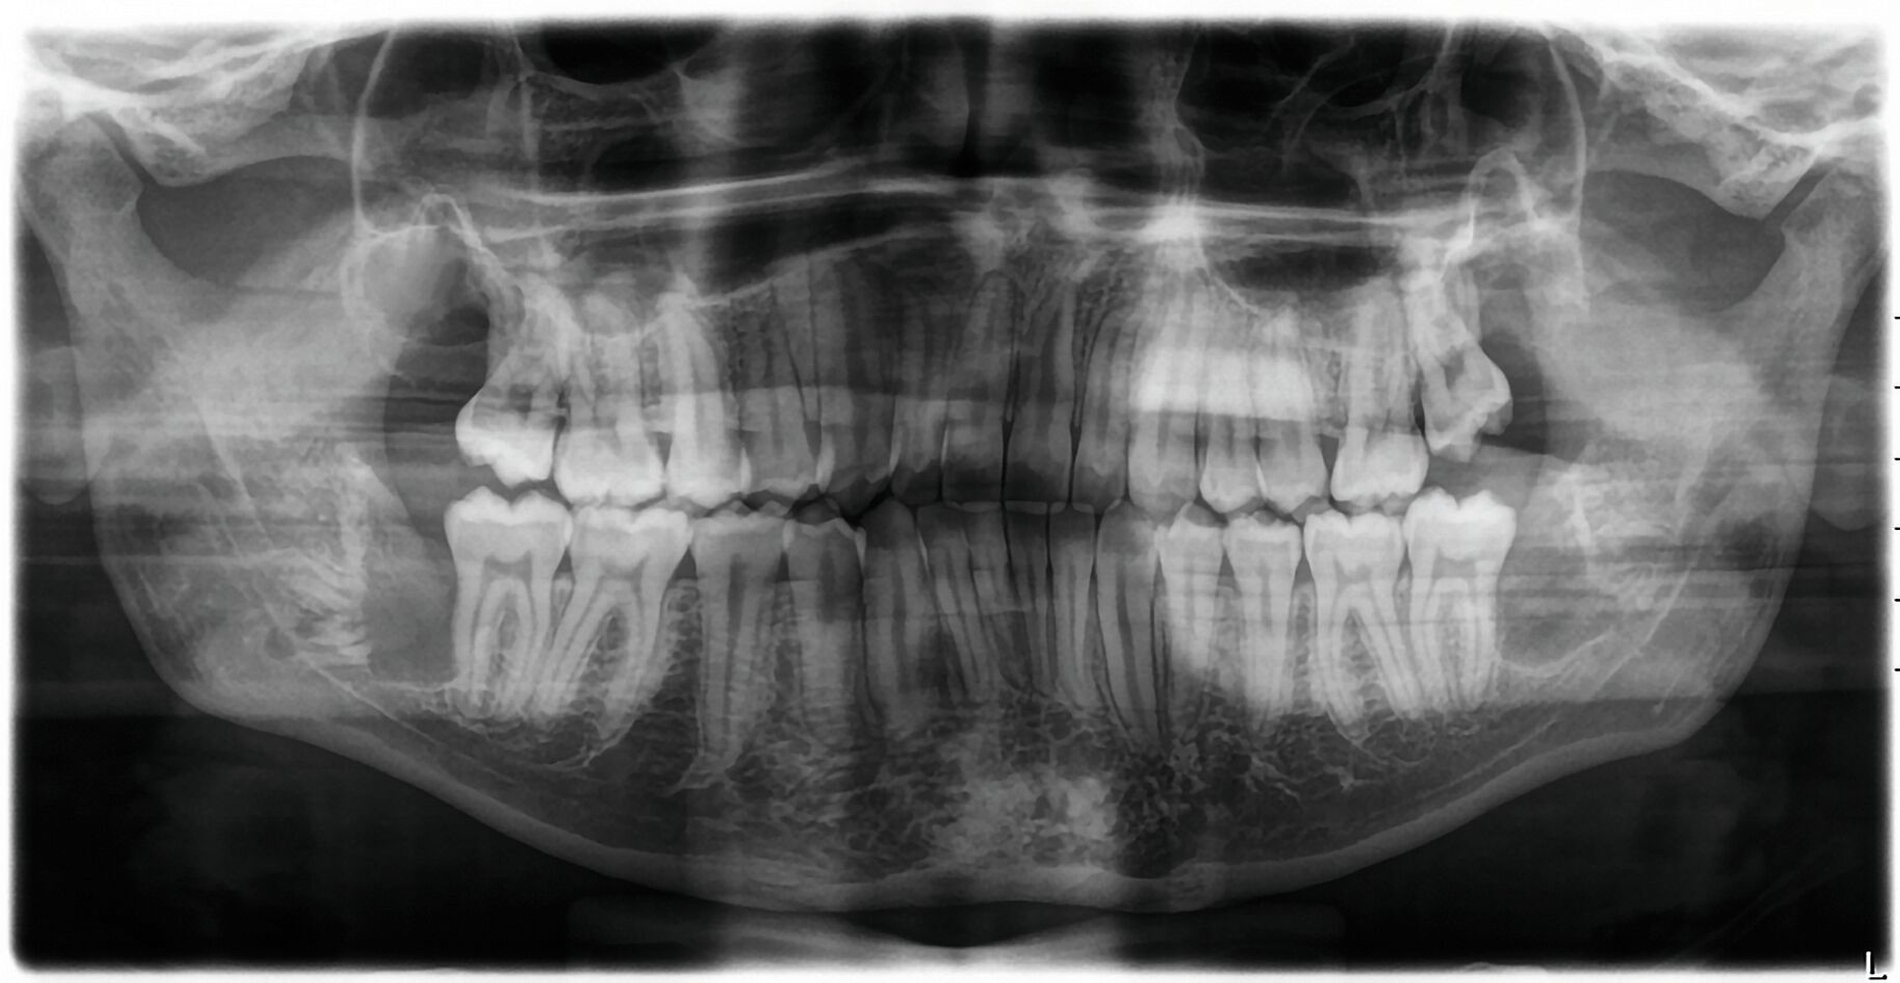

Neben der ausführlichen Anamnese und der klinischen Untersuchung ist eine röntgenologische Untersuchung wichtig. Zur Übersicht kann eine zweidimensionale Panoramaschichtaufnahme angefertigt werden, um die Lage und Angulation der Weisheitszähne sowie deren Beziehung zu ihren anatomischen Nachbarstrukturen beurteilen zu können [ARö/DGZMK, 2022; DGMKG, 2019].

Abbildung 1 zeigt ein Fallbeispiel einer Panoramaschichtaufnahme eines 18-jährigen Patienten mit den genannten röntgenologischen Anzeichen einer engen Lagebeziehung zum Nervkanal, zum einen in Regio 38, aber auch in Regio 48. Zudem befinden sich in Regio 18 und 28 unklare weitere zahnähnliche Strukturen.

Bei solch besonderen Risikosituationen kann gemäß den S2k-Leitlinien „Dentale digitale Volumentomographie“ und „Operative Entfernung von Weisheitszähnen“ eine dreidimensionale Bildgebung in Form einer digitalen Volumentomografie oder einer Computertomografie durchgeführt werden [ARö/DGZMK, 2022; DGMKG, 2019]. Mit der präziseren Visualisierung von Karies, Wurzelresorptionen, Wurzelpositionen und deren Morphologie sowie der Lagebeziehung zu den Nachbarstrukturen kann man die differenzialtherapeutische Entscheidungsfindung, die detaillierte Risikoaufklärung des Patienten und die Operationsplanung verbessern. Außerdem kann die Bildgebung vom Behandler intraoperativ genutzt werden, um sich zu orientieren.

Im vorliegenden Fallbeispiel wurde eine dreidimensionale Bildgebung durchgeführt, da sowohl im Ober- als auch im Unterkiefer Risikohinweise bestanden. Zum einen lag eine unmittelbare Lagebeziehung zum N. alveolaris inferior und somit ein erhöhtes Risiko einer Nervschädigung vor, zum anderen bestanden Hinweise auf Lageanomalien und mögliche Doppelanlagen im Oberkiefer, die in der zweidimensionalen Bildgebung kaum beurteilt werden konnten. In der DVT zeigte sich in Regio 48 ein intraradikulärer Verlauf des N. alveolaris inferior durch die Wurzel des nach mesial gekippten und retinierten Zahnes 48 sowie eine perikoronare Aufhellung, die nah an die distale Wurzel des Zahnes 47 reicht (Abbildung 2).